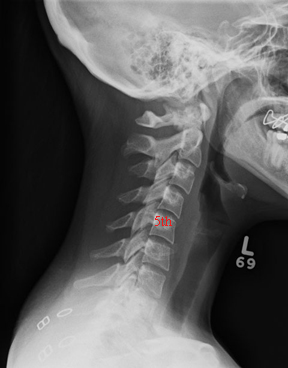

Images with red objects have the red object as the heart. Of note, the sternum does not completely cover the heart, the intercostal spaces are greater than the ribs, and on the silhouette, the heart is 9.52% of the boxed area.